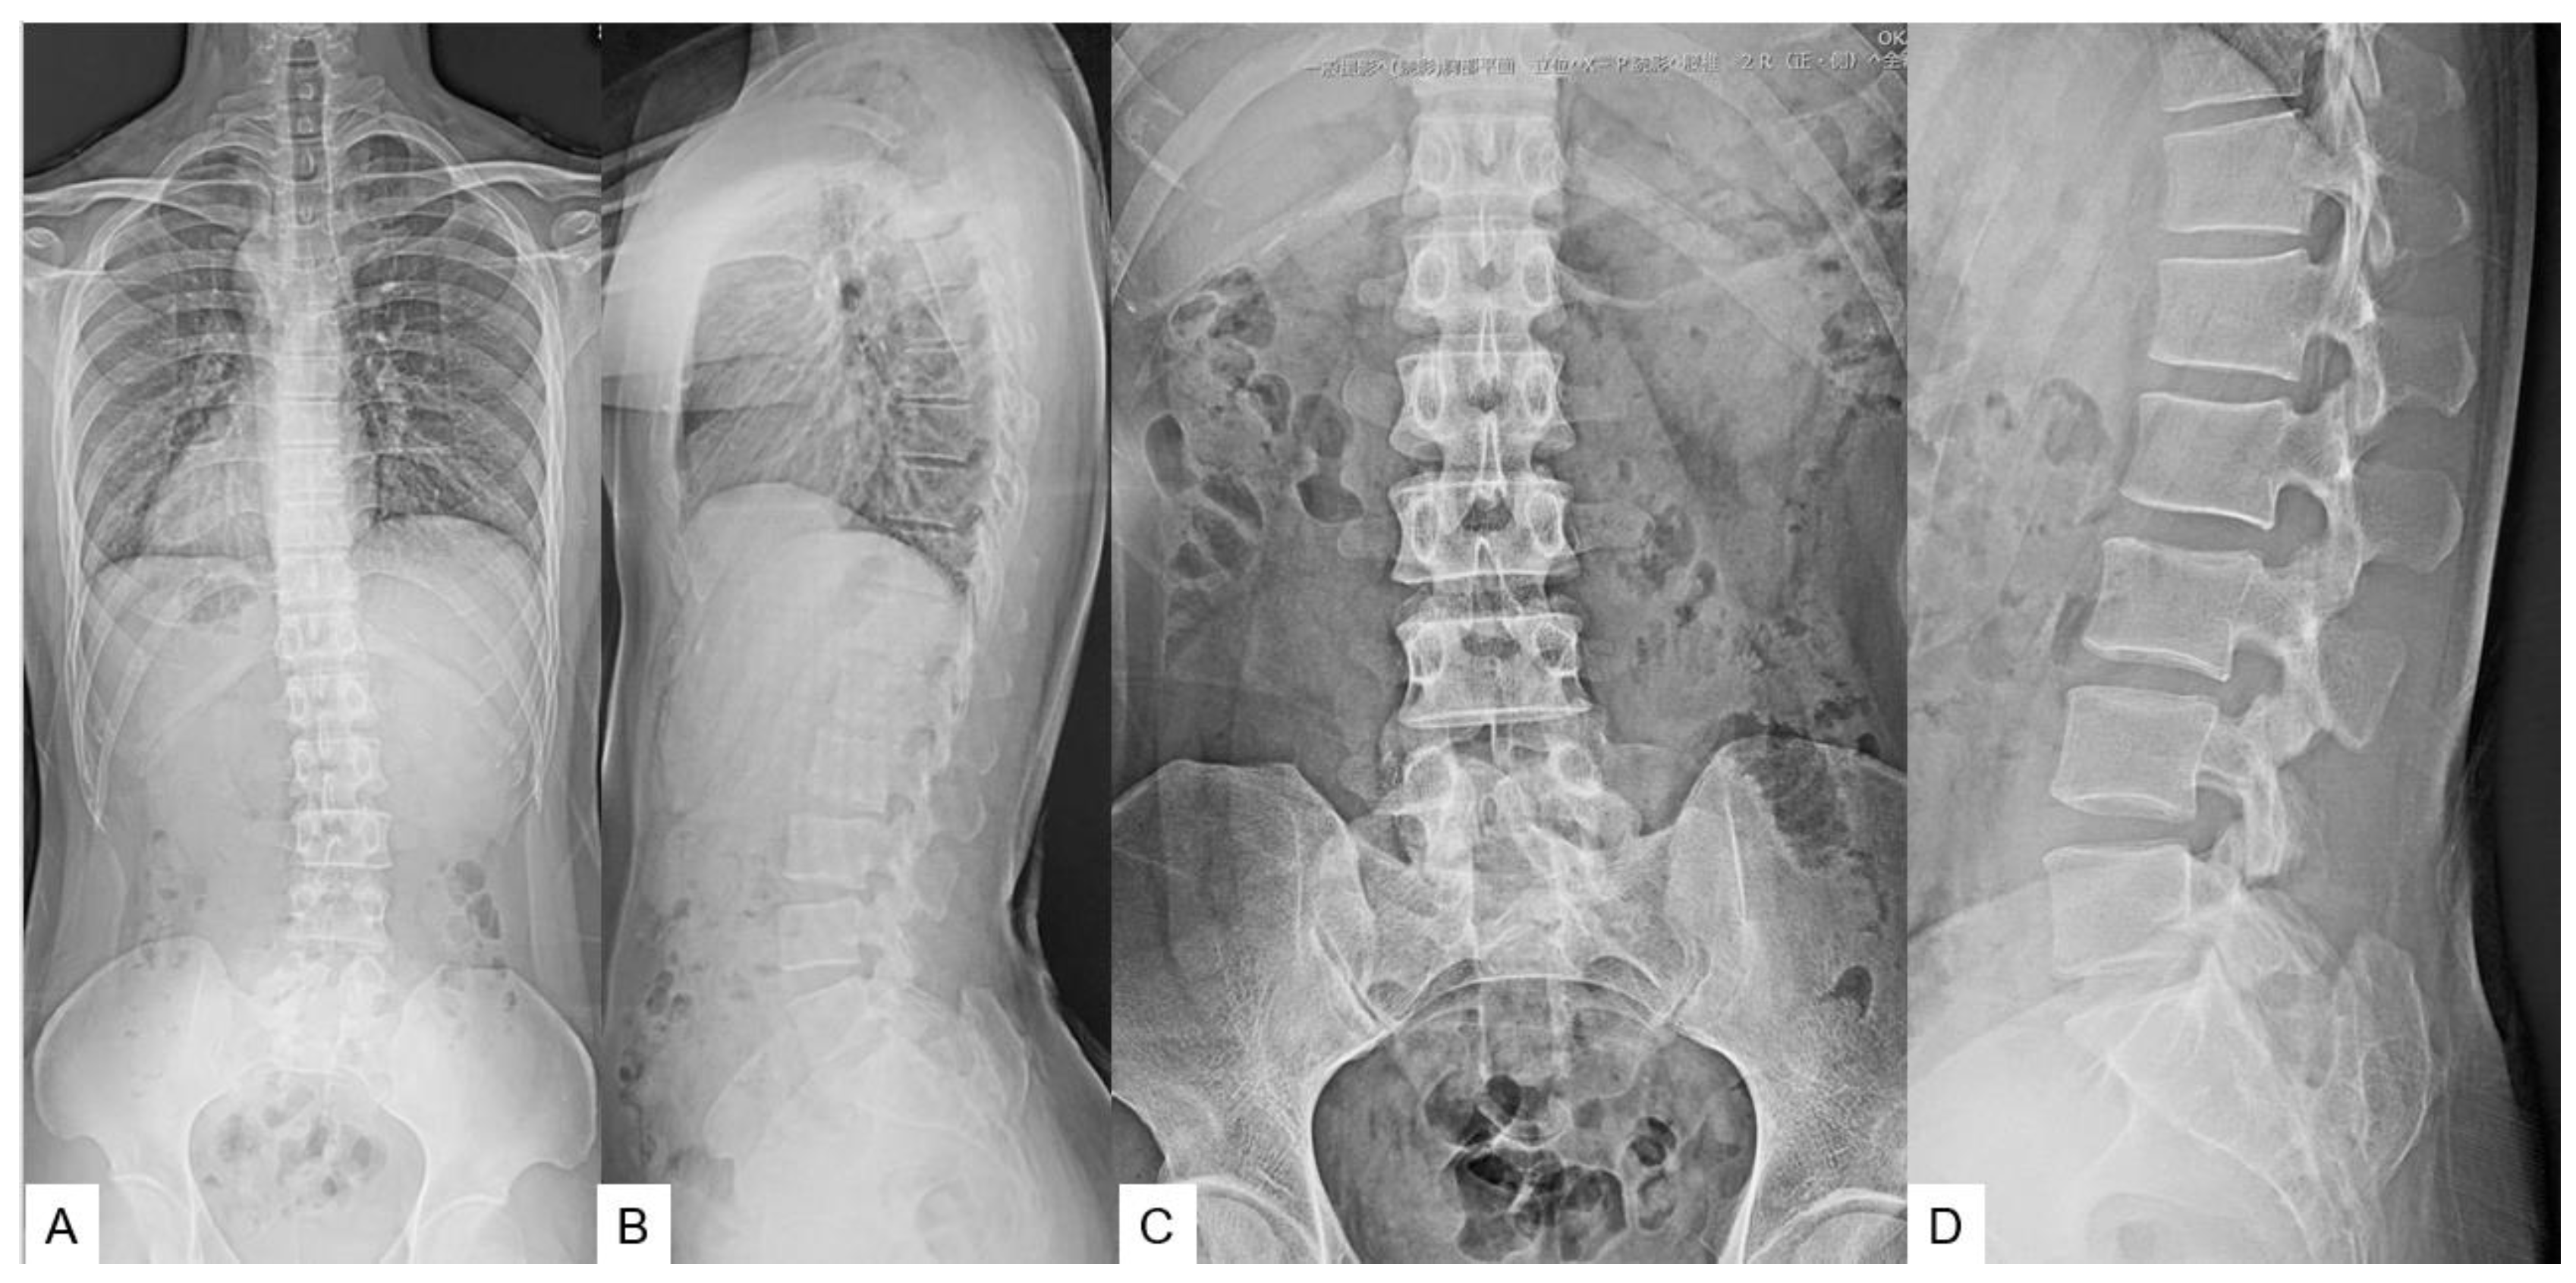

3. Case 2 33 years old male, tethered cord syndrome, conventional technique